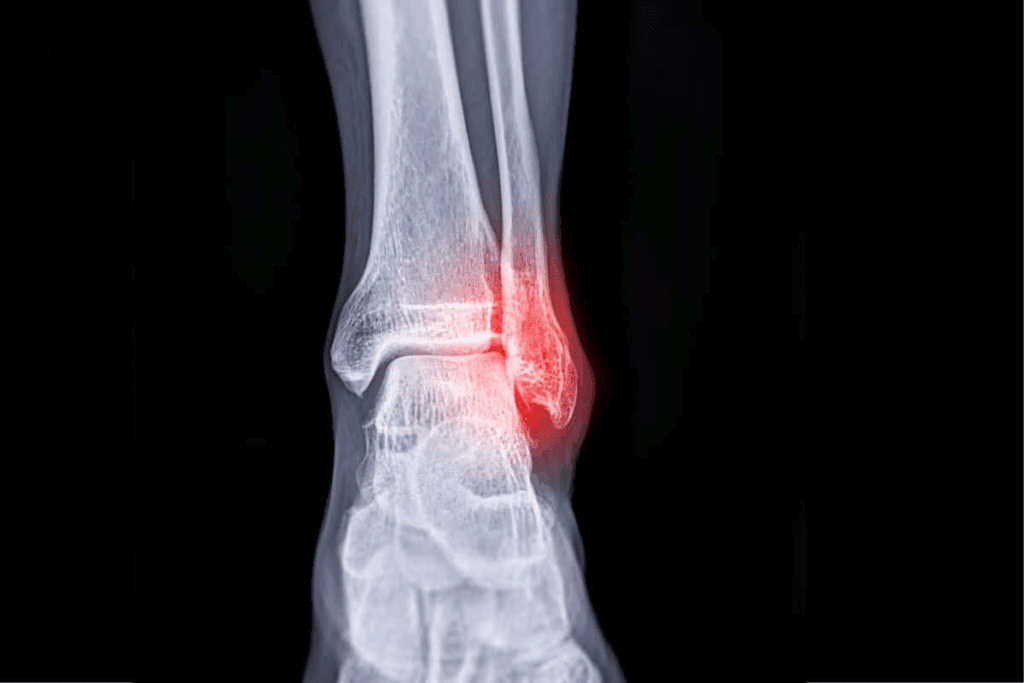

Medical Imaging in Tendonitis Diagnosis

Advanced medical imaging has made diagnosing tendonitis more accurate. These tools help doctors see tendons and tissues clearly. This makes it easier to check if tendons are healthy.

X-Rays and Their Limited Role in Tendonitis

X-ray for tendonitis is not the main tool. But, it helps rule out other problems like fractures or calcium in tendons. X-rays are good for bones and finding calcium in tendons.

But, X-rays can’t see soft tissues well. So, they’re used with other tests or doctor checks for a full diagnosis.